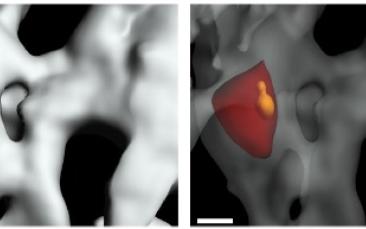

There is no easy cure for obesity nowadays, as scientists have an incomplete understanding of what controls body weight. With ERC funding, Dr Lydia Lynch has returned to Europe from the US to work on an entirely new field in the treatment of obesity.There is no easy cure for obesity nowadays, as scientists have an incomplete understanding of what controls body weight. With ERC funding, Dr Lydia Lynch has returned to Europe from…There is no easy cure for obesity nowadays, as scientists have an incomplete understanding of what controls body weight. With ERC funding, Dr Lydia…There is no easy cure for obesity nowadays, as scientists have an incomplete understanding of what controls body weight. With ERC funding, Dr Lydia Lynch has returned to…There is no easy cure for obesity nowadays, as scientists have an incomplete understanding of what controls body weight…Career -